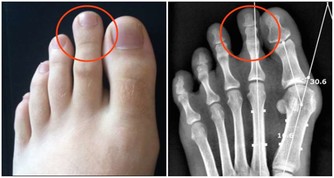

脾臟是身體最大的淋巴器官,流動的方式是靠著肌肉收縮,如果不往左側睡淋巴會停擺,因此靠左側睡淋巴液會因重力流入脾臟,循環更加有效率也能幫助毒素排出。